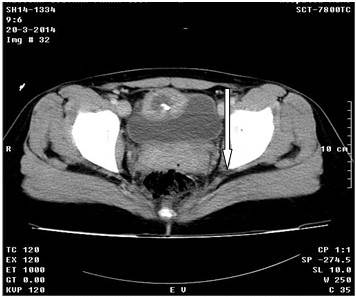

Continuaron las investigaciones con una tomografía axial computarizada de abdomen e hipogastrio, simple y contrastada, donde se observó ambos riñones normales, en fase nefográfica, sin litiasis y sin hidronefrosis, así como el parénquima conservado. Por encima de la vejiga y a la derecha de la línea media, se observó una imagen hipodensa de 38X41mm, con una pared gruesa de 12mm que aumentó su densidad con la administración de contraste, y con elemento metálico en su interior que impresionó ser un clip de ligadura, que al parecer pinzaba la cara anterior de la vejiga, todo ello relacionado con reacción inflamatoria y absceso a ese nivel. Además de la vejiga en repleción, se observó el útero de tamaño normal, anejos normales y densidades homogéneas. (Figuras 4 y 5). A la paciente se le realizó laparoscopia diagnóstica, con lo que se corroboró el diagnóstico. Se realizó cirugía para extracción del clip metálico. La evolución de la paciente fue satisfactoria.